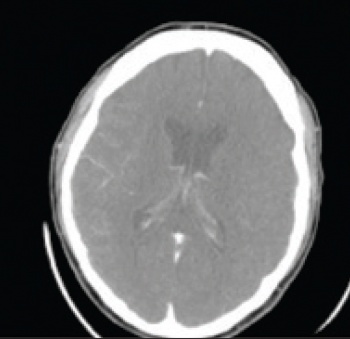

See Figures 1(i)-3(ii) for images of a successful endovascular therapy case.